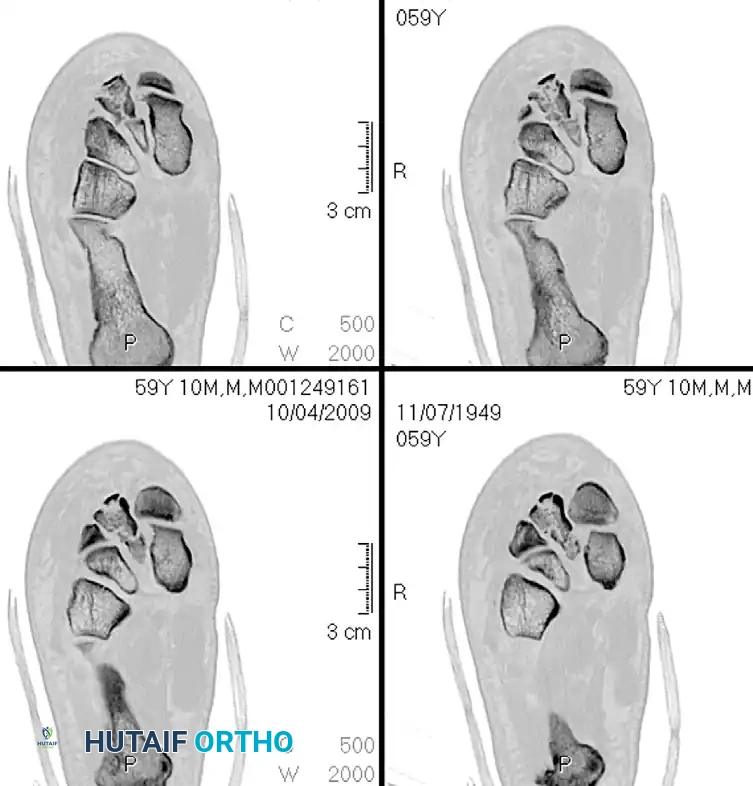

The stability of the tarsometatarsal (TMT) joint complex relies on both its intrinsic bony architecture and a robust ligamentous network. The base of the second metatarsal is recessed proximally between the medial and lateral cuneiforms, creating a "keystone" configuration that locks the midfoot.

Crucially, there is no transverse ligament connecting the bases of the first and second metatarsals. The primary stabilizing structure is the Lisfranc ligament, a thick, oblique interosseous band originating from the lateral aspect of the medial cuneiform and inserting onto the medial base of the second metatarsal. Disruption of this ligament, either through direct crush injuries or indirect axial loading on a plantarflexed foot, leads to catastrophic destabilization of the medial column.

Classification of Tarsometatarsal Injuries

The Myerson modification of the Quenu and Kuss classification system remains the standard for categorizing Lisfranc fracture-dislocations. While it does not strictly dictate the surgical approach, it provides a vital framework for understanding the energy of the injury and the pattern of displacement.